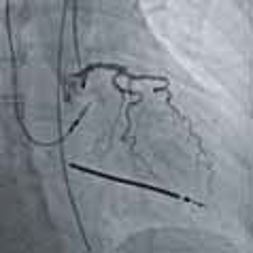

4. Численні програми для кількісного аналізу зображень, програми для покращення візуалізації стентів, програми для аналізу дозового навантаження, функції отримання, аналізу та накладання 3D-зображень, програми для оцінки перфузії судин та широкі можливості постробробки – прокриють усі, навіть найвибагливіші потреби.